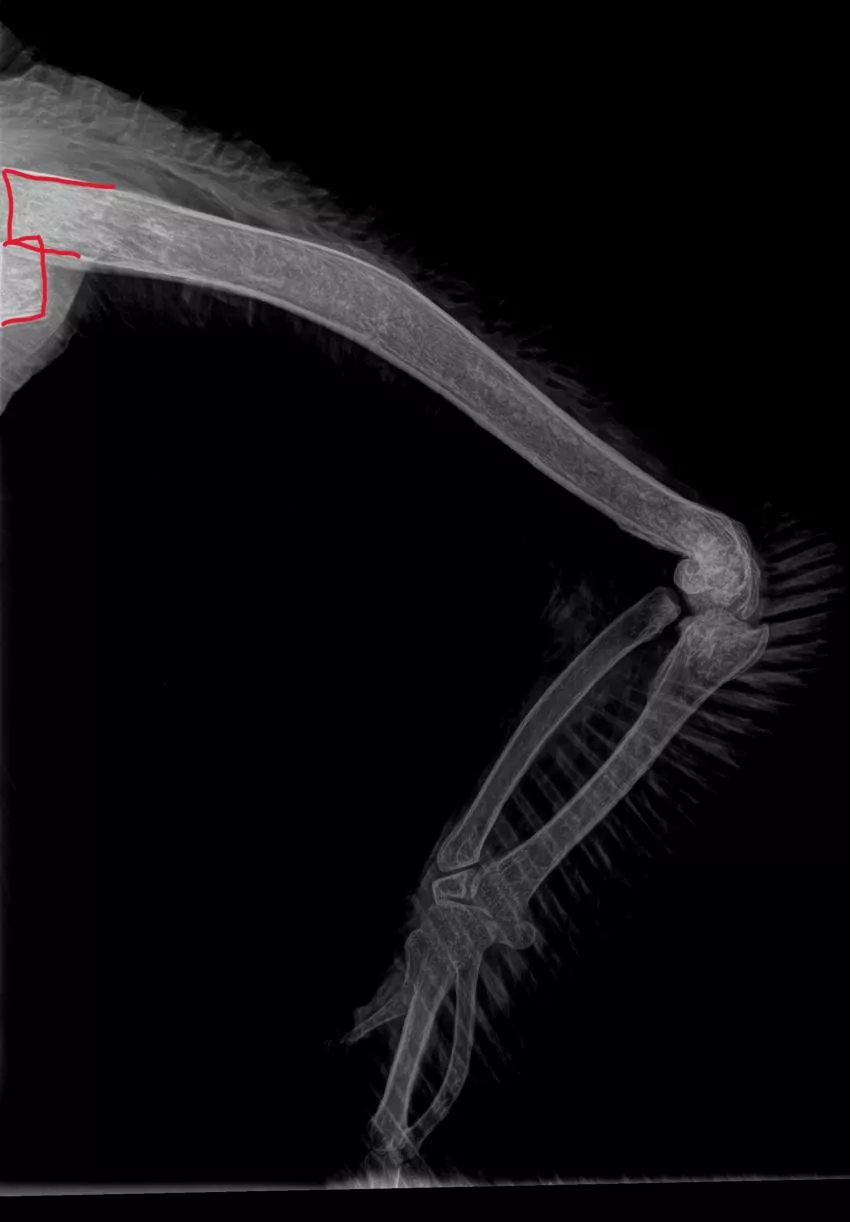

On the morning of June 8, Hattiesburg Zoo animal care team members noted thatTwig was presenting a wing droop on her left side. The team, under the direction of zoo veterinarian Julia MacGregor, immobilized Twig for a full exam including bloodwork and x-rays, which showed a broken proximal humerous in the left wing with no other injuries noted.

“It was a clean break with minimal displacement or movement of the bone fragments and the bone did not break through the skin, which made Twig a good candidate for repair,” MacGregor said.

Twig now has a permanent plate and screws holding the broken bone together, giving long-term stability of the affected bone. She did well through the surgery and recovery process.

Twig is currently housed in the zoo’s Hoof Stock Quarantine area, and she is checked on daily to assess any signs of discomfort or stress. MacGregor and her team have fully anesthetized Twig at the Hattiesburg Zoo to take x-rays, assess the incision site, determine proper healing and then re-bandaged to keep her wing still, which will allow for optimal healing.